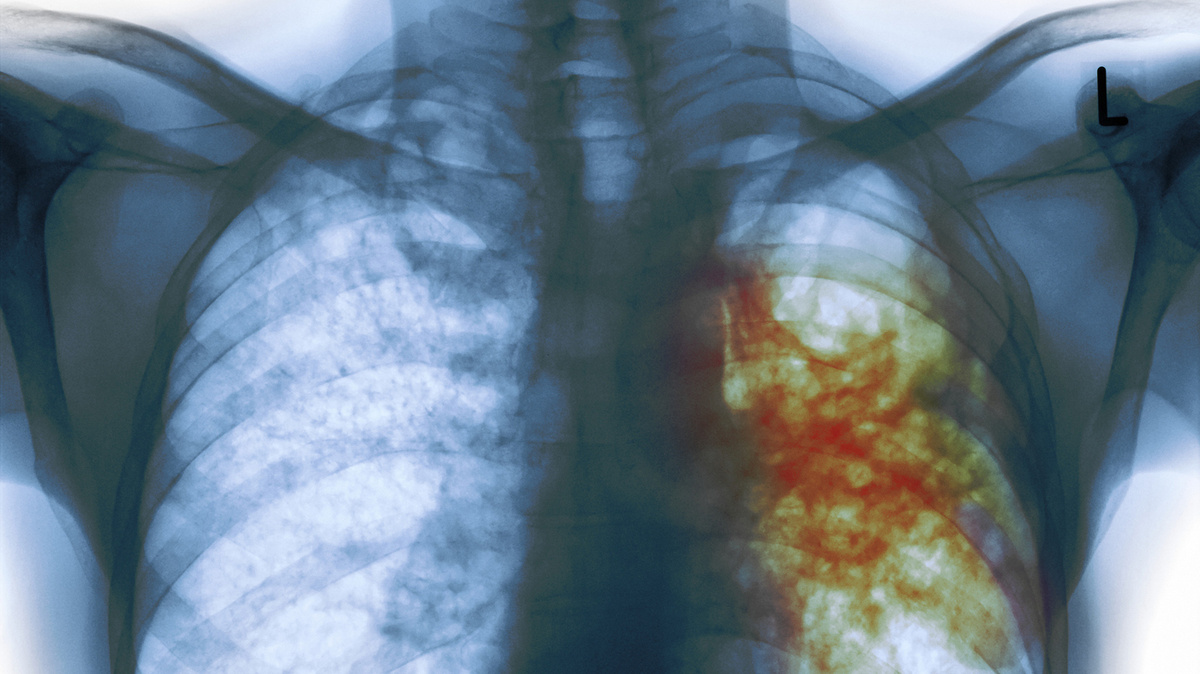

С начала 2000-х годов Россия добилась впечатляющего прогресса в борьбе с туберкулезом: заболеваемость снизилась в три раза . Однако, несмотря на этот успех, борьба с болезнью сталкивается с серьёзными вызовами, среди которых — ВИЧ и рост лекарственно-устойчивых форм туберкулеза .

По данным портала «Если быть точным» , в 2023 году каждый третий новый пациент страдал от форм туберкулеза, устойчивых к стандартным препаратам. Это делает лечение более сложным, длительным и дорогостоящим. По эффективности лечения Россия пока уступает мировым показателям: 67% против 88% в мире .